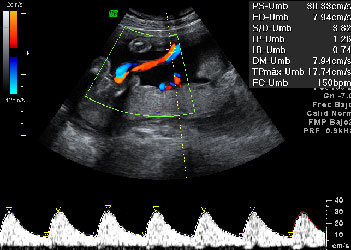

Ecografía doppler.

Se basa en el efecto Doppler (diferencia de frecuencia en las ondas en función de si se están acercando o alejando).

Al recibir ondas de una frecuencia transmitida de un fluido en movimiento, la frecuencia es mayor si se está acercando a la fuente y menor si se aleja. La diferencia entre estas frecuencia da la frecuencia Doppler.

Este efecto se utiliza para la exploración del flujo sanguíneo.

Hay 3 tipos:

Doppler pulsado: se transmiten impulsos cortos y se espera el eco para observar un cambio de frecuencia, el cual es directamente proporcional a la velocidad del fluido.

Doppler color: es la más utilizada, permite ver el flujo de sangre que pasa por los vasos en el estudio. En caso de que la sangre se aproxime a la sonda, se suele representar de color rojo, y si se aleja, de color azul.

Doppler potencia: se ven coloreados los vasos, pero no se tiene en cuenta el sentido de la sangre. Es más sensible a la velocidad del fluido, pero se suelen generar algunos artefactos, como el de vibración tisular.